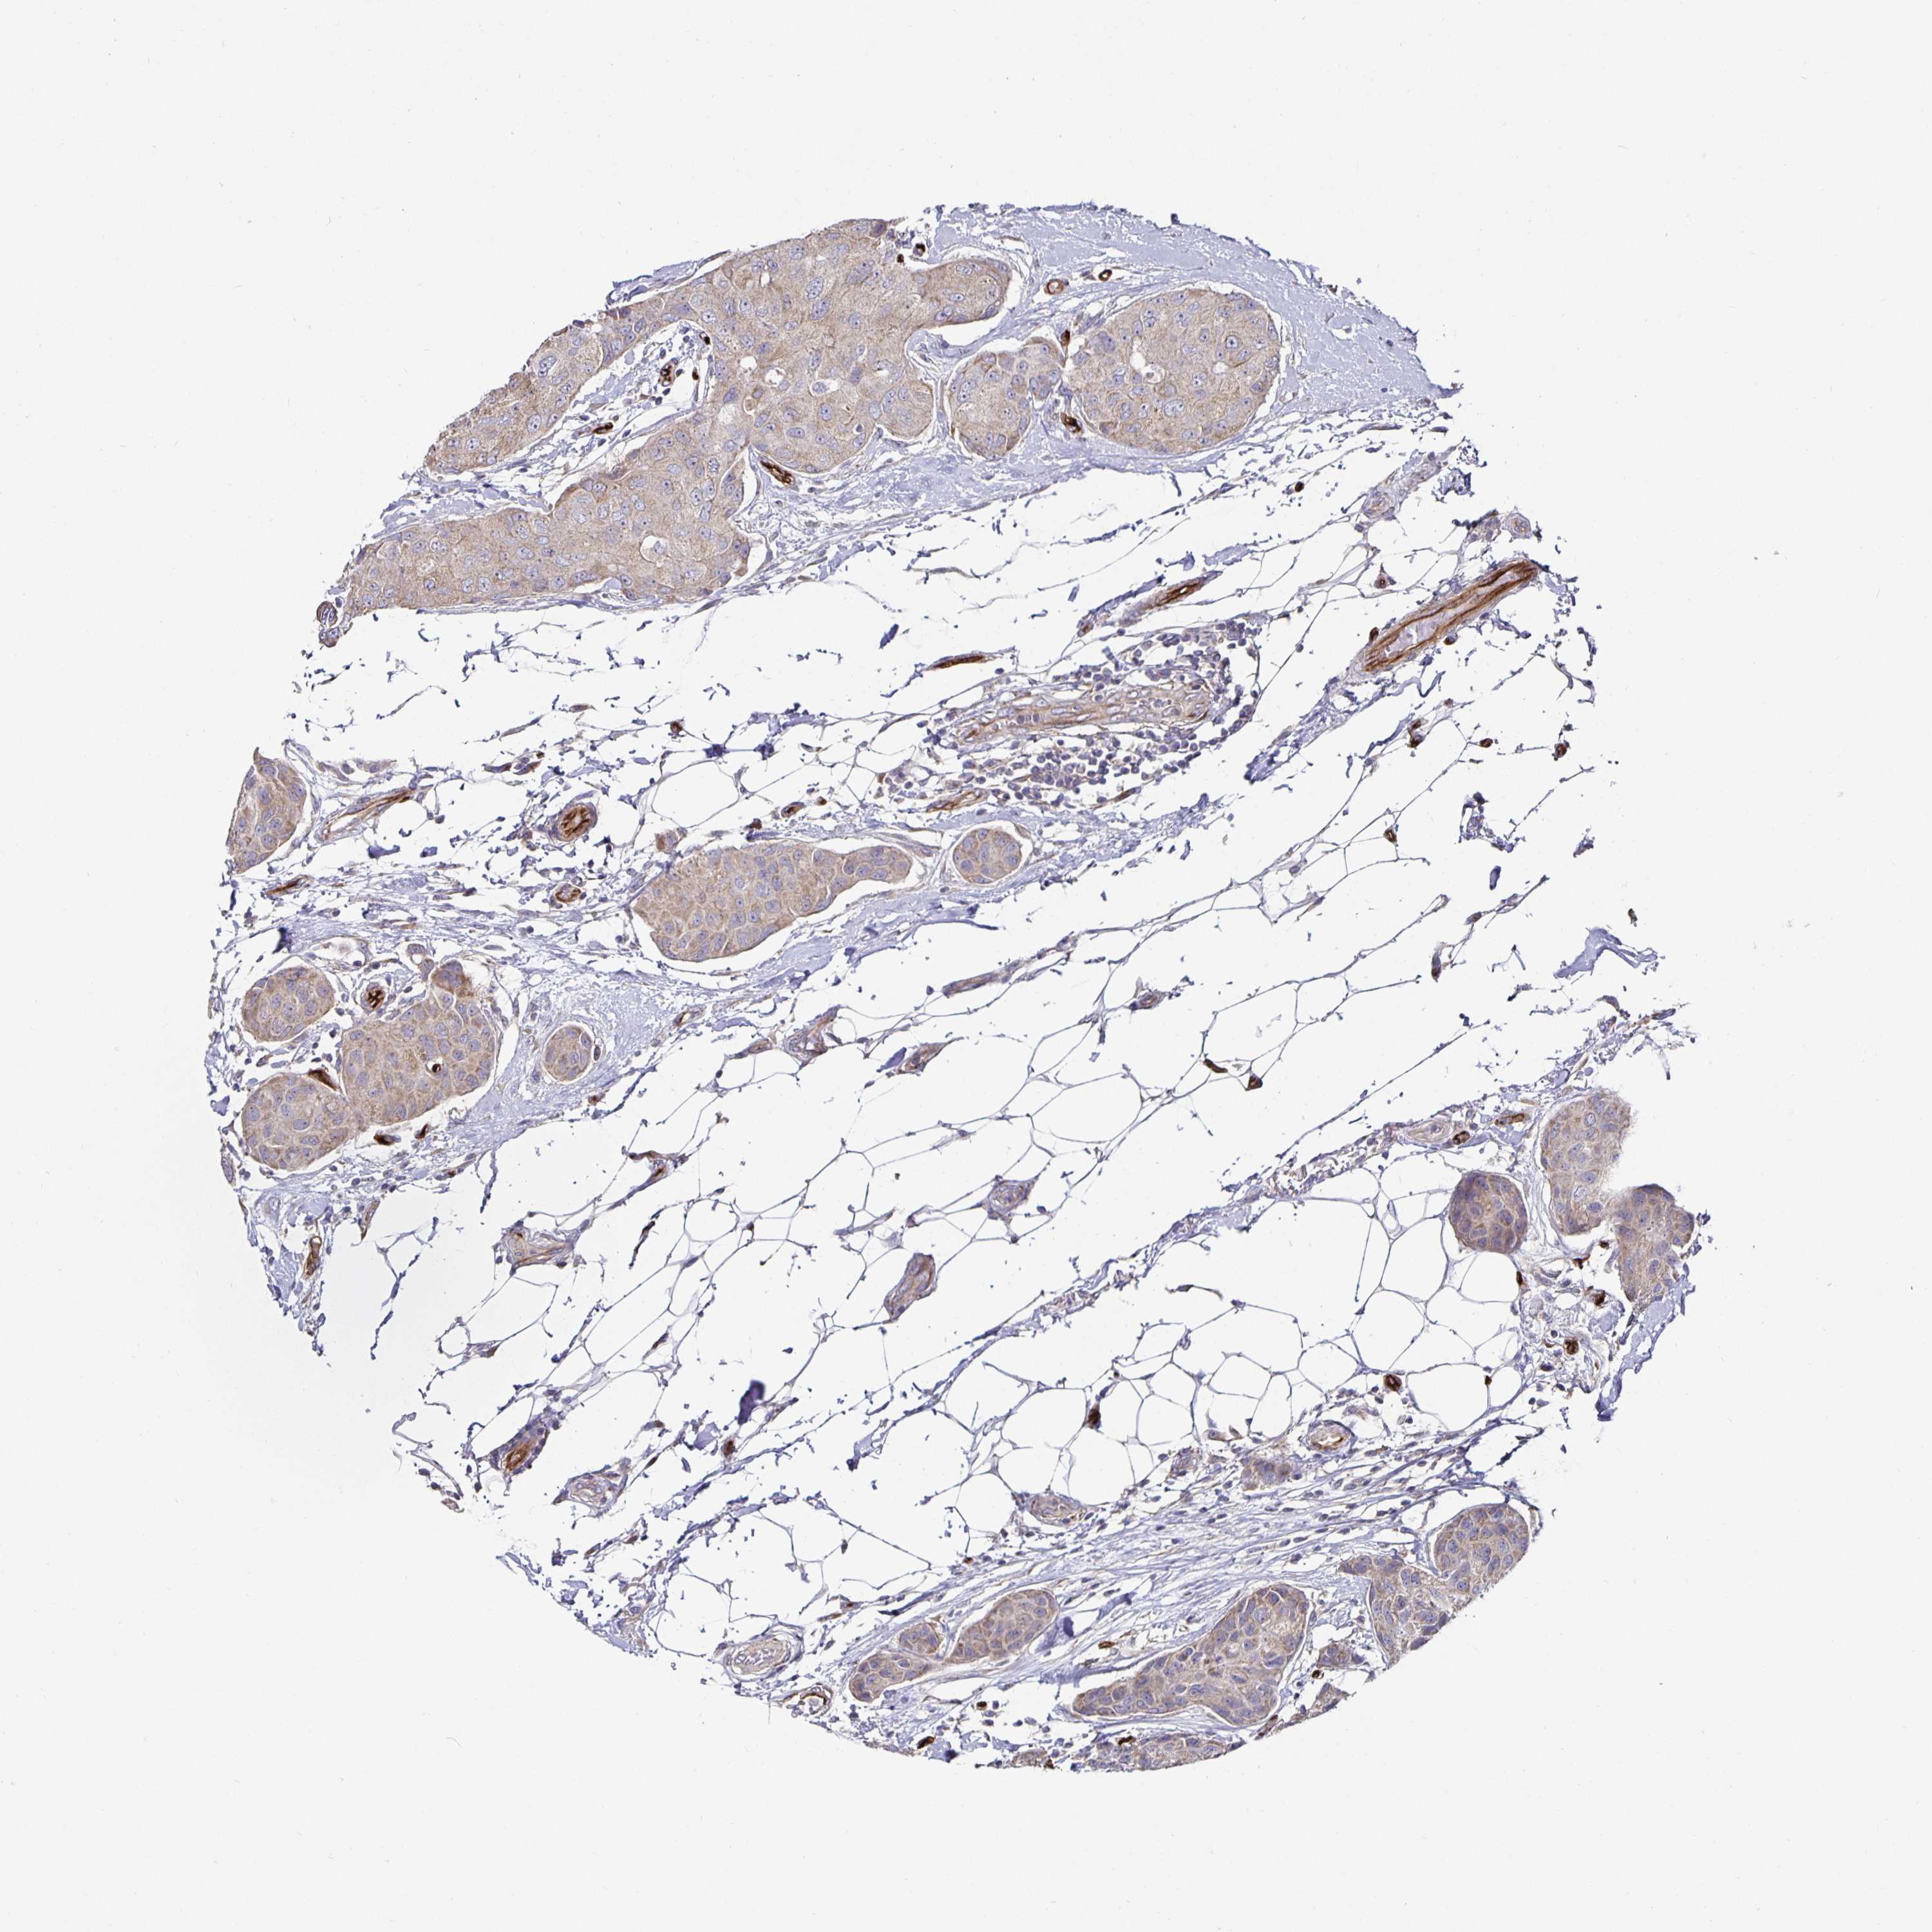

BRCA TCGA BRCA VALIDATION PROTEIN EXPRESSION